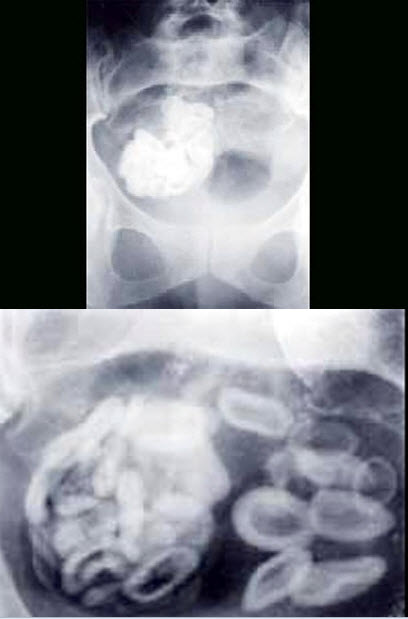

10、多项选择题

男,55岁,上腹饱胀不适2月,结合图像,最可能的诊断是()

A.正常表现

B.食管癌

C.食管静脉曲张

D.胃炎

E.胃癌

点击查看答案